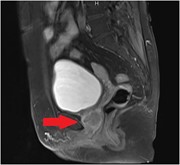

Suppurative appendicitis presenting as acute scrotum confounded by a testicular appendage

Syed Shumon and others

Journal of Surgical Case Reports, Volume 2016, Issue 3, March 2016, rjw027, https://doi.org/10.1093/jscr/rjw027